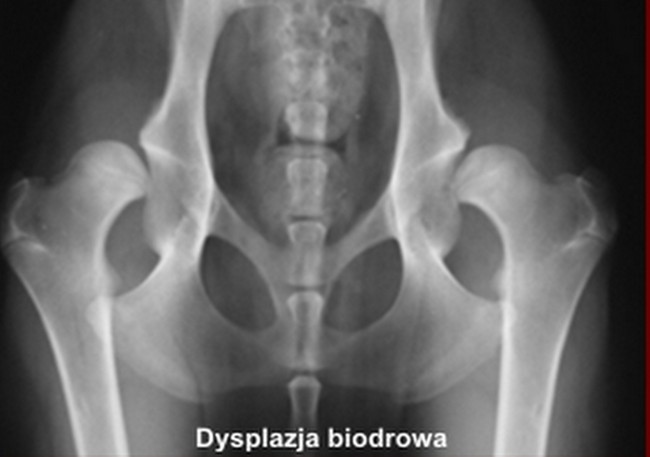

Rozpoznanie dysplazji łokciowej możliwe jest wyłącznie na podstawie zdjęcia rtg. Wykonuje się je w znieczuleniu ogólnym, podobnie jak w przypadku dysplazji biodrowej, przy czym odmienne jest oczywiście ułożenie psa do badania. Wynik oprócz kwalifikacji psa do hodowli posłuży do wyboru najlepszej w danym przypadku metody leczenia.

Zdjęcie rtg, podobnie jak w przypadku dysplazji biodrowej, określa stopień upośledzenia stawu: